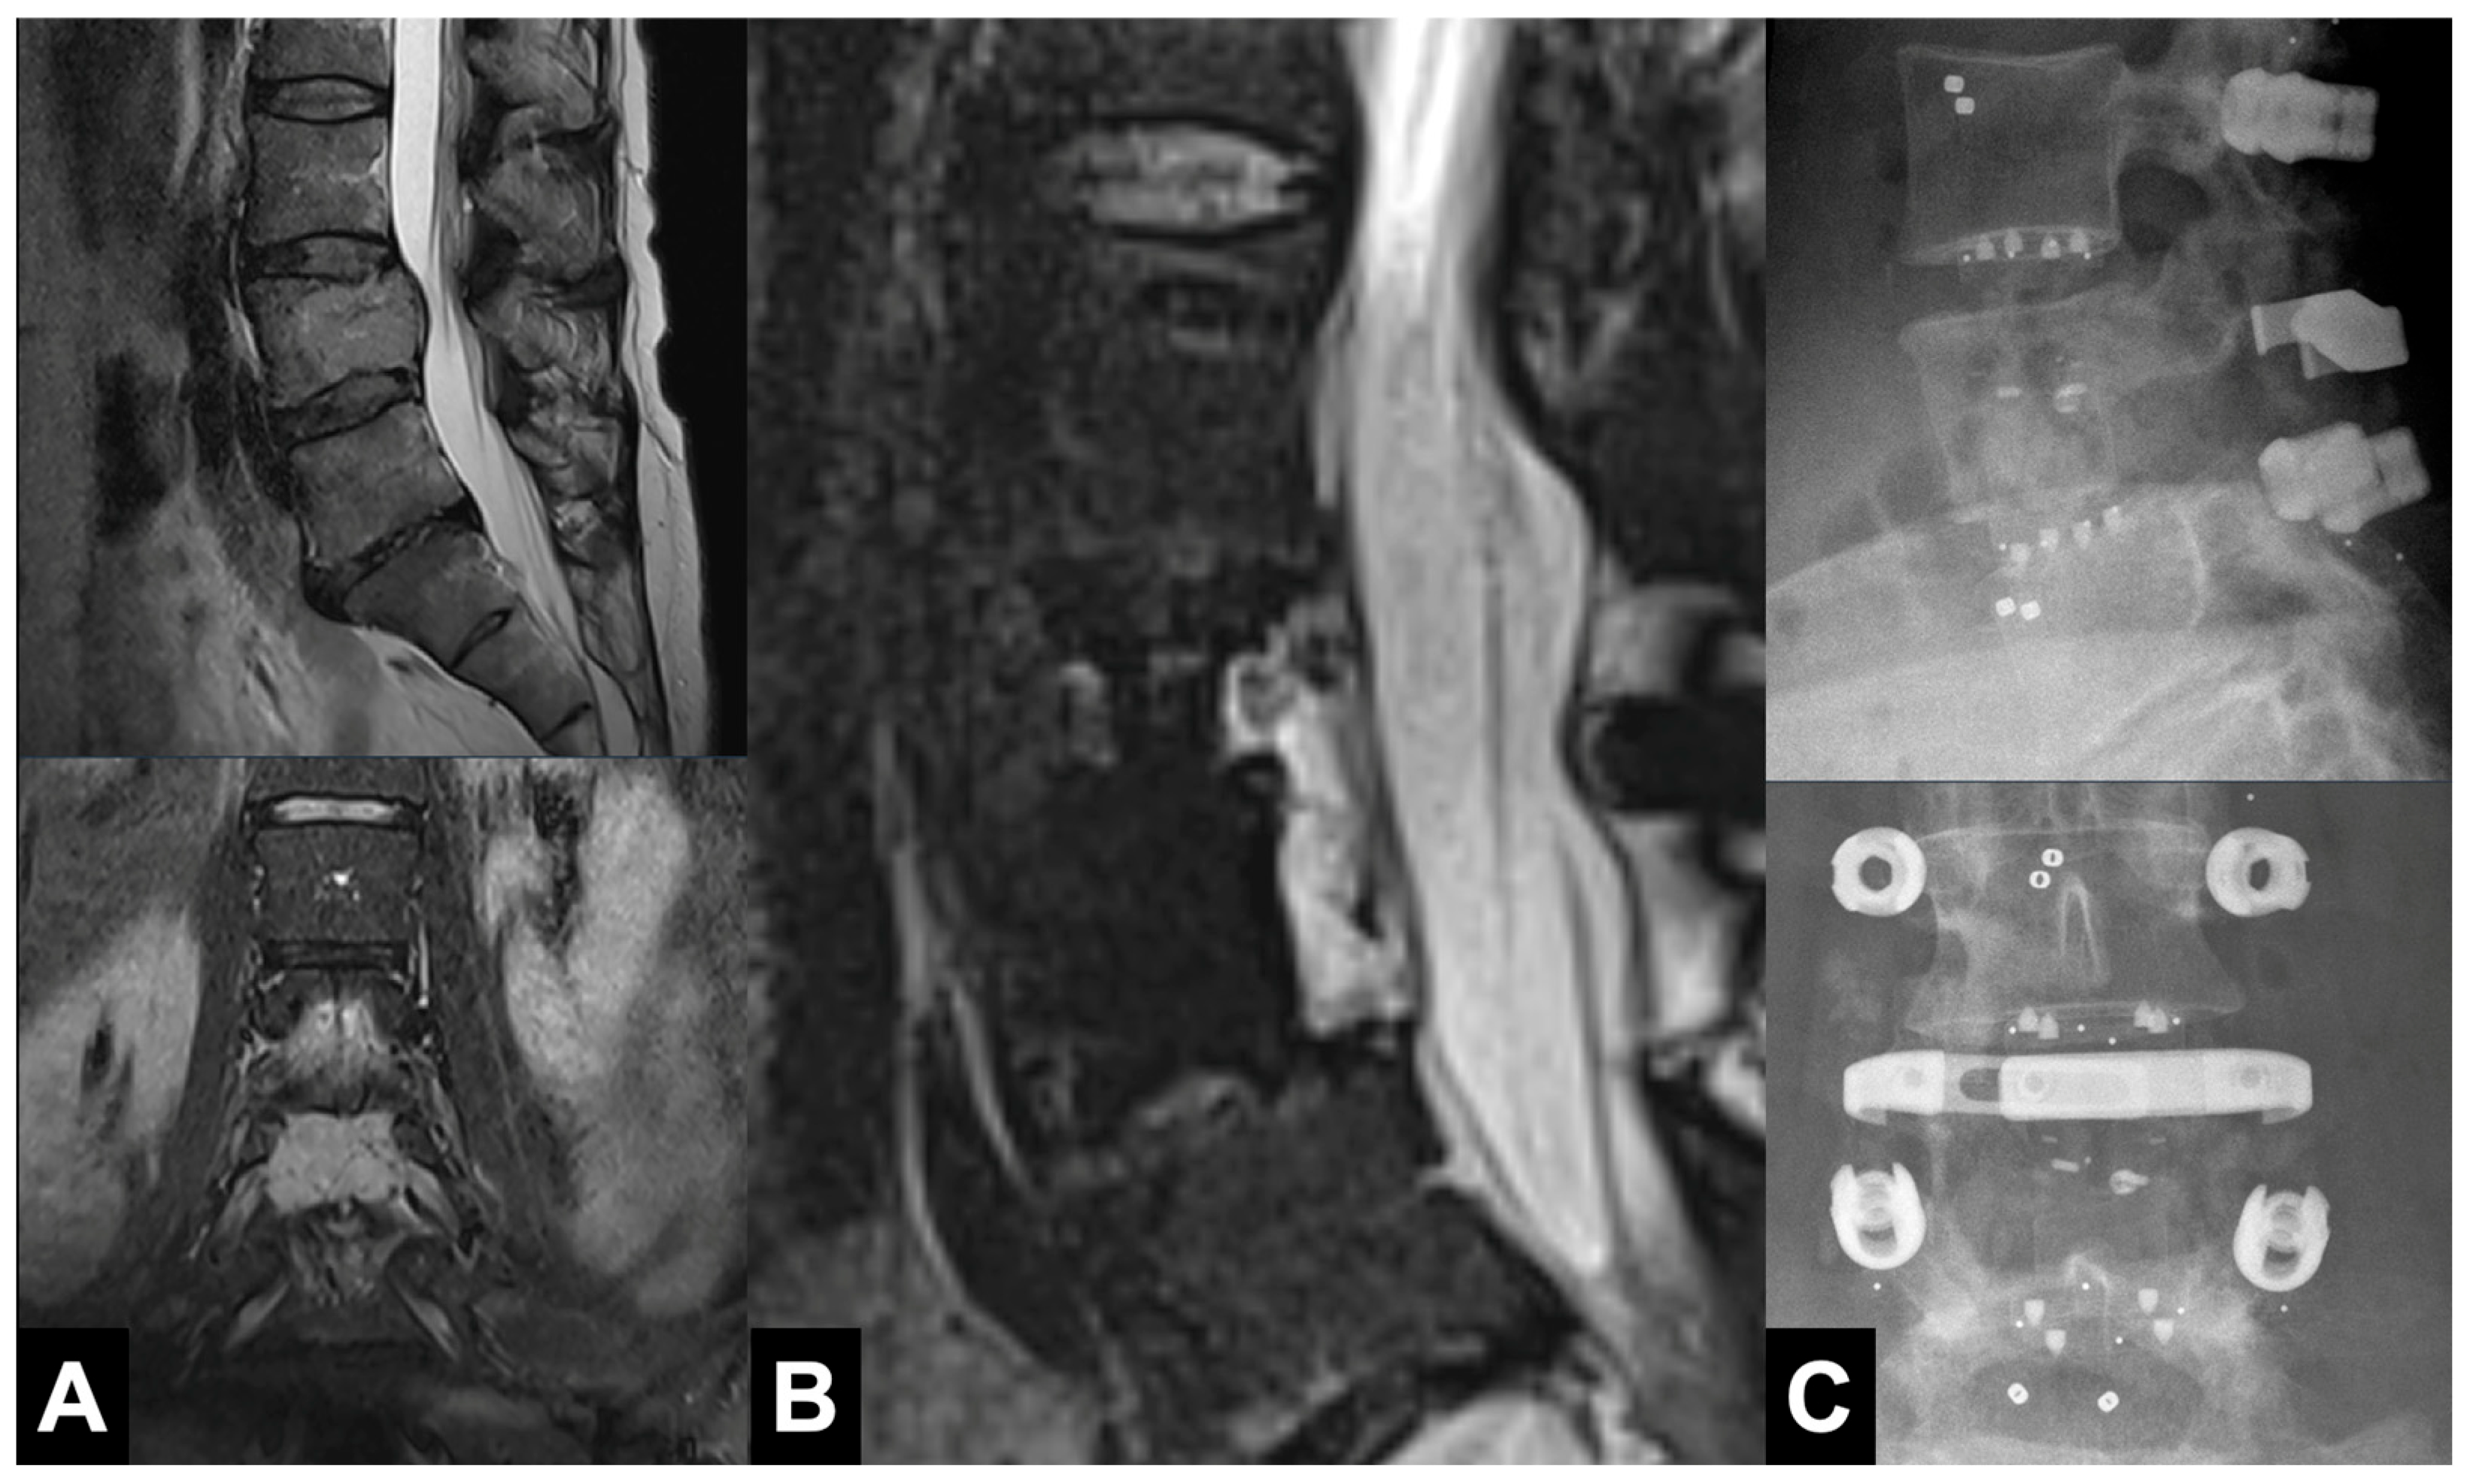

3.2. Radiographic Outcomes

3.3. Clinical Outcomes